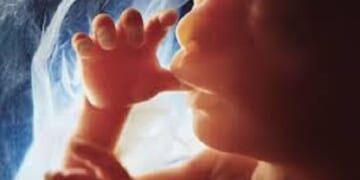

A Natrona County judge has temporarily blocked Wyoming’s Human Heartbeat Act, a law aimed at protecting unborn babies from abortion once the baby’s heartbeat is detectable. Natrona County District Judge Dan Forgey issued the temporary…